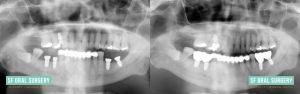

Patient 2

The patient presented with numerous decayed and broken teeth and expressed a strong desire for improved oral health. Ultimately, we placed five implants, resulting in a complete restoration of her dentition with a beautiful set of teeth. This case was conducted under the care of Dr. Rittenbach and in collaboration with Dr. Courtney Fitzpatrick.